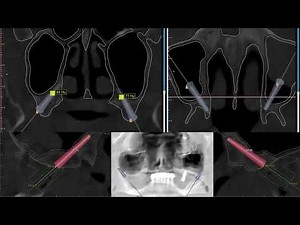

Guided Pterygoid Implant 的热门建议 |

Drilling 50s - Pterygoid Implants

- Blue Sky Plan Implant Validation